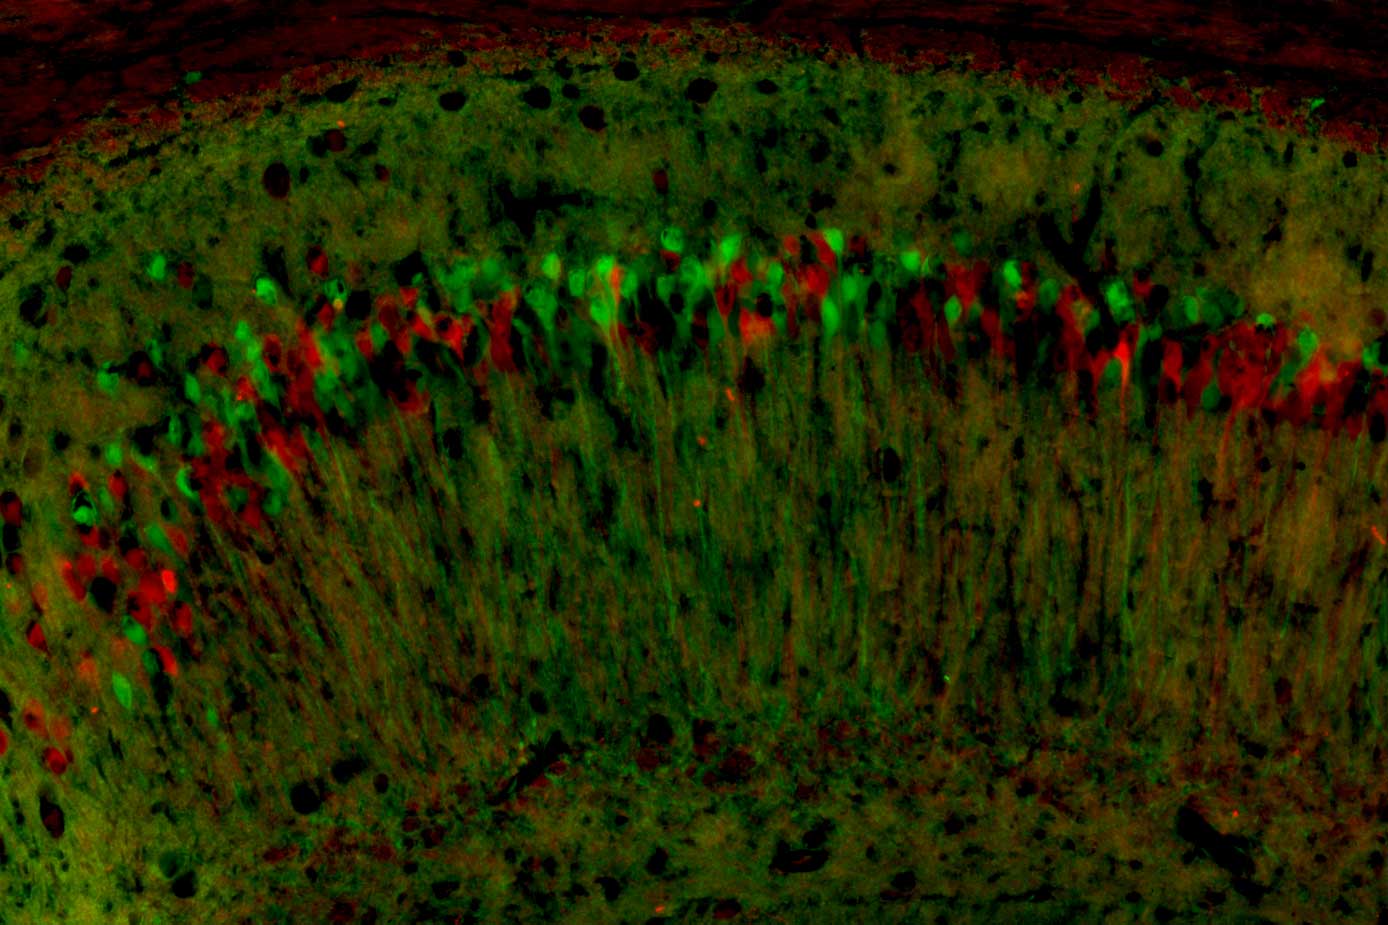

A microscopic image of neurons expressing the mother's X chromosomes in green, and the father’s X chromosomes in red.

A microscopic image of neurons expressing the mother’s X chromosomes in green, and the father’s X chromosomes in red. Credit: Arturo Moreno.